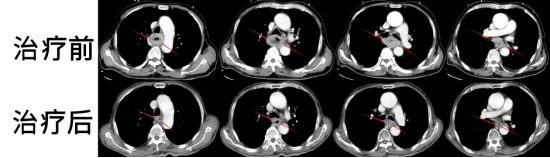

圖注:胸部CT掃描治療前后比對。上排為治療前,可見食管癌偏心病灶,增厚的食管腫瘤病灶阻塞食管;下排為治療后,食管癌病灶縮退,食管形態(tài)基本恢復(fù)正常